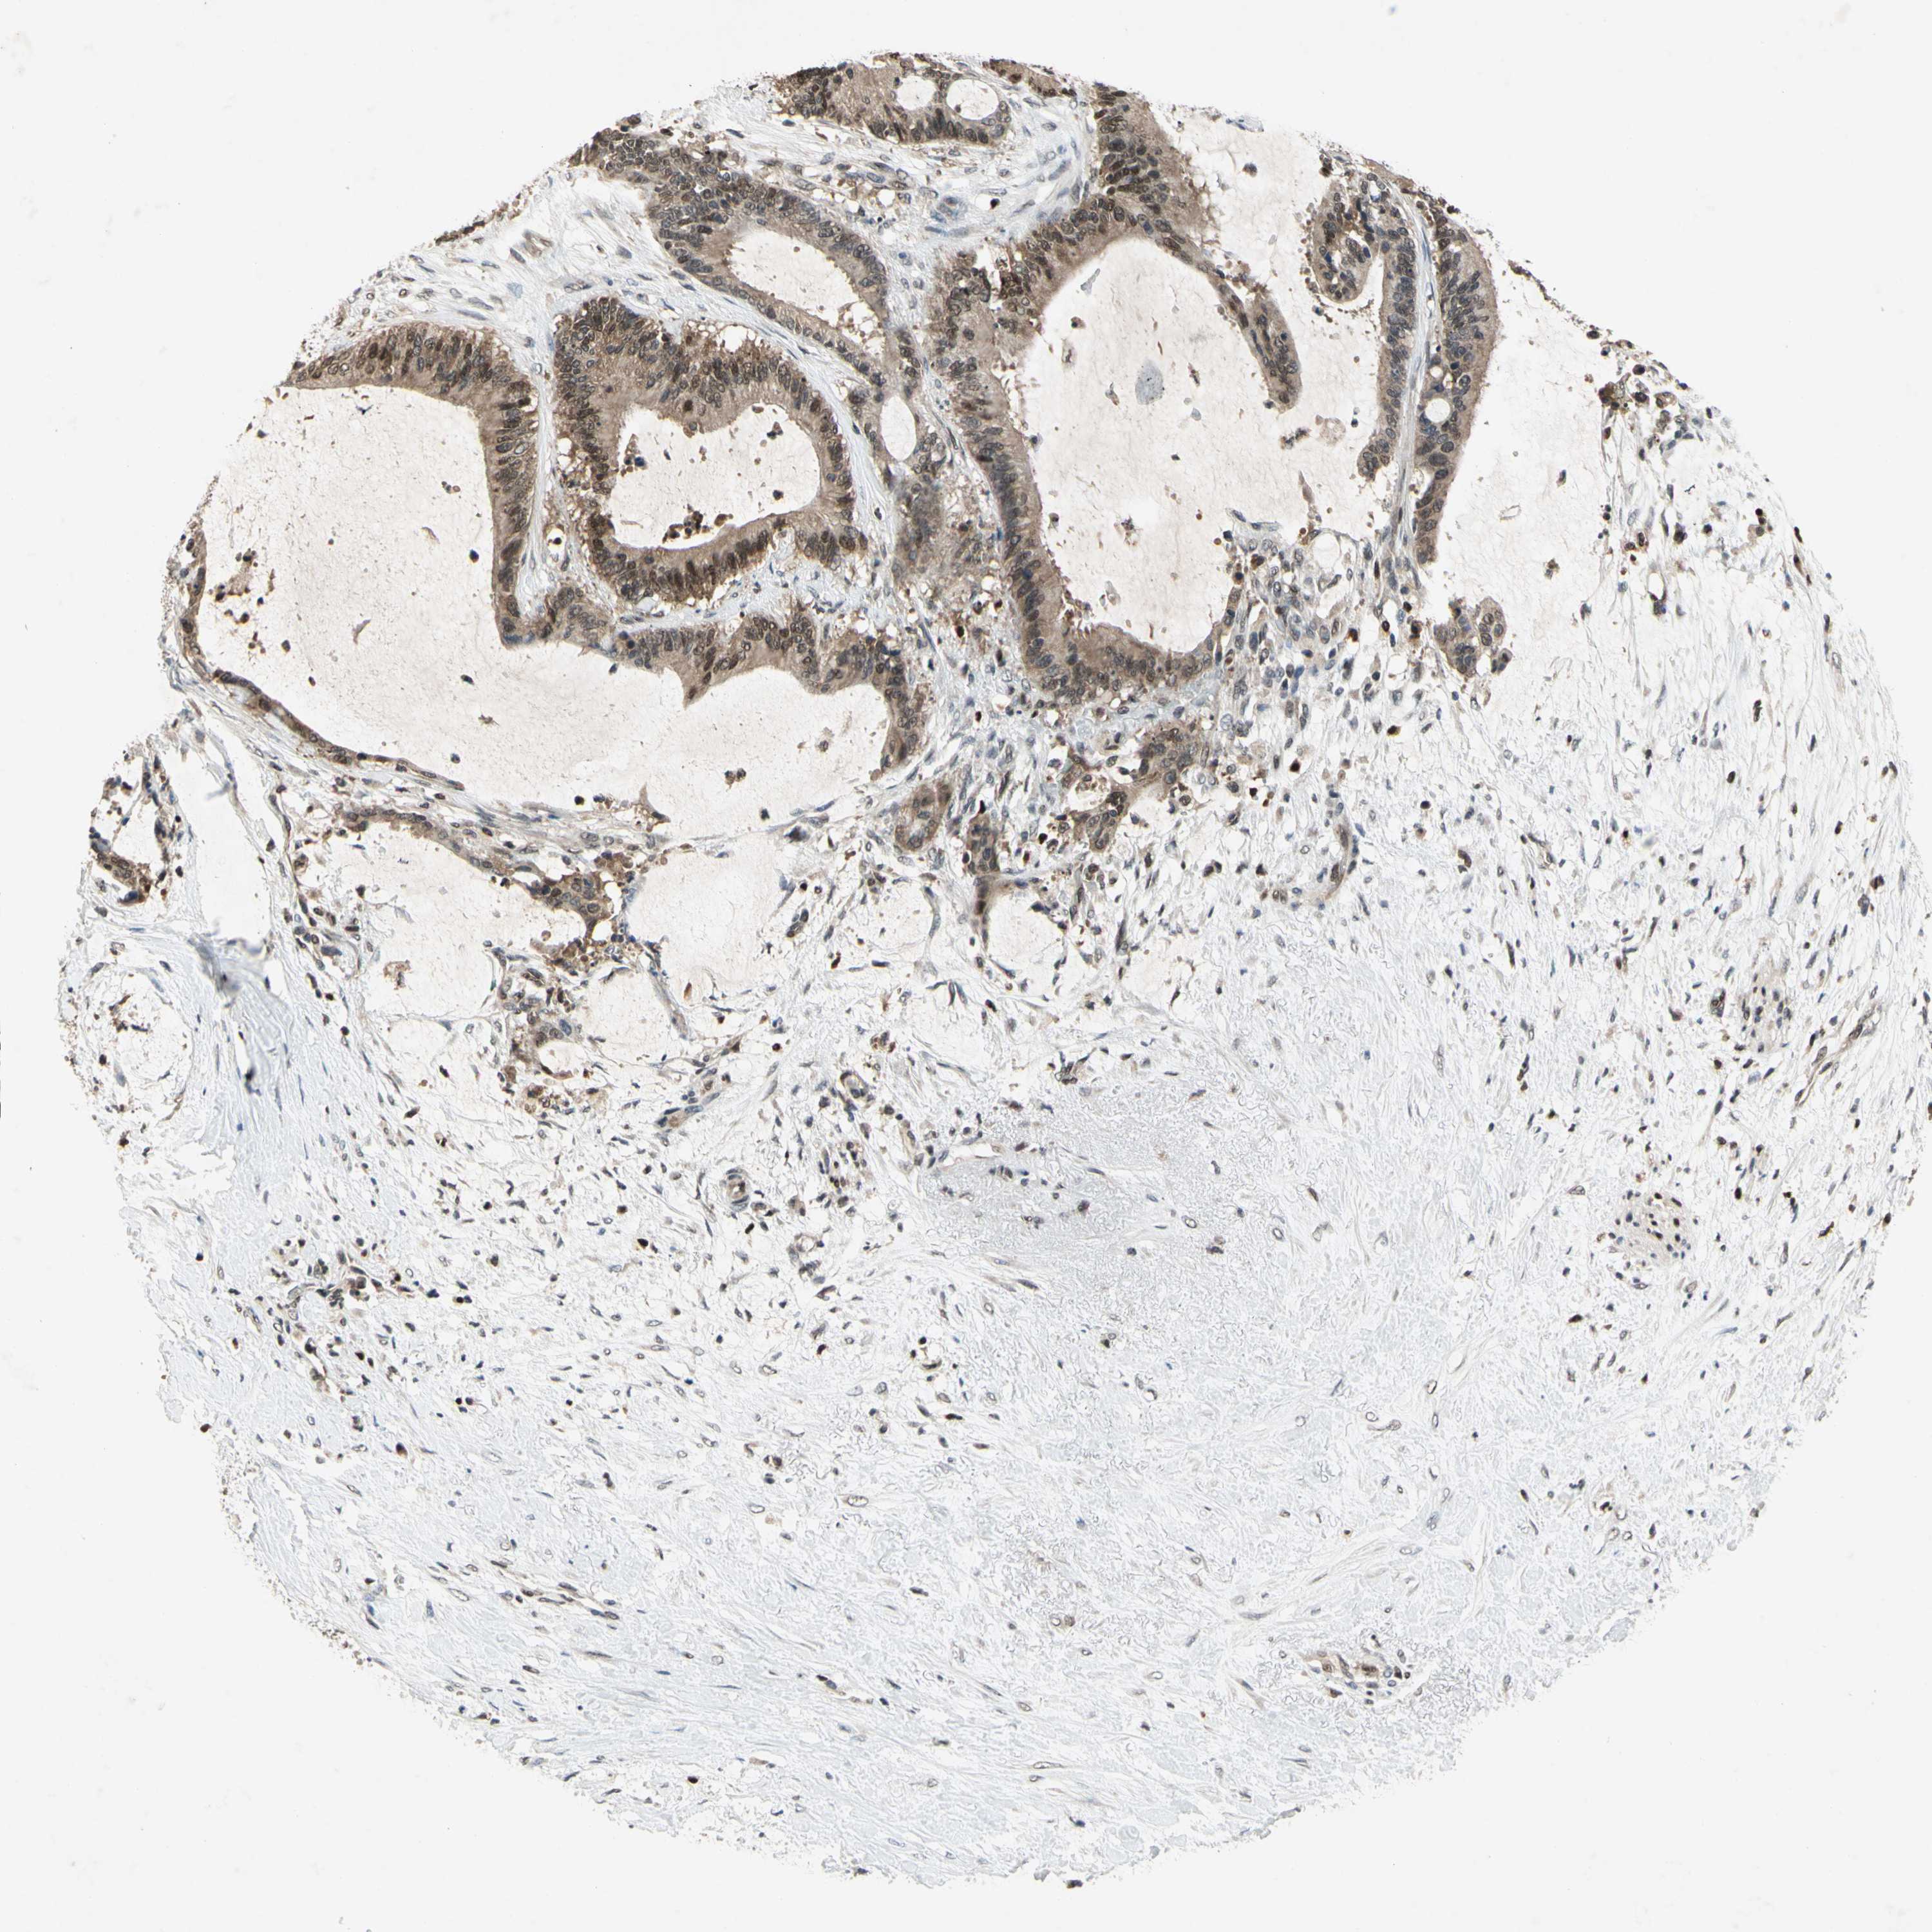

LIVER CANCER - Protein expressioni

A mouse-over function shows sample information and annotation data. Click on an image to view it in a full screen mode. Samples can be filtered based on level of antibody staining by selecting one or several of the following categories: high, medium, low and not detected. The assay and annotation is described here.

Note that samples used for immunohistochemistry by the Human Protein Atlas do not correspond to samples in the TCGA dataset.

Antibody stainingi

Antibody staining in the annotated cell types in the current human tissue is reported as not detected, low, medium, or high, based on conventional immunohistochemistry profiling in selected tissues. This score is based on the combination of the staining intensity and fraction of stained cells.

Each image is clickable and will lead to virtual microscopy that enables deeper exploration of all samples and also displays staining intensity scores, fraction scores and subcellular localization as well as patient and tissue information for each sample.

Antibody HPA001538

Antibody CAB008632

Staining

High

Medium

Low

Not detected

Intensity

Strong

Moderate

Weak

Negative

Quantity

>75%

75%-25%

<25%

None

Location

Nuclear

Cytoplasmic/membranous

Cytoplasmic/membranous,nuclear

Cholangiocarcinoma

Carcinoma, Hepatocellular, NOS